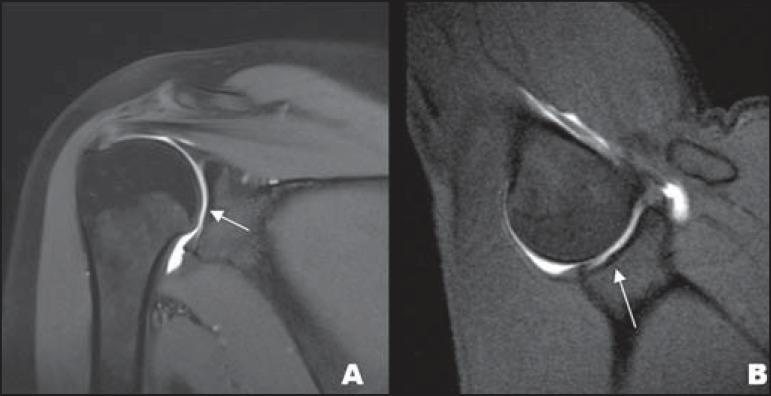

Magnetic resonance imaging has revolutionized the diagnosis of shoulder lesions, in many cases becoming the method of choice. However, anatomical variations, artifacts and the particularity of the method may be a source of pitfalls, especially for less experienced radiologists. In order to avoid false-positive and false-negative results, the authors carried out a compilation of imaging findings that may simulate injury. It is the authors' intention to provide a useful, consistent and comprehensive reference for both beginner residents and skilled radiologists who work with musculoskeletal magnetic resonance imaging, allowing for them to develop more precise reports and helping them to avoid making mistakes.

磁共振成像彻底改变了肩部病变的诊断方式,在许多情况下已成为首选方法。然而,解剖变异、伪影以及该方法的特殊性可能会成为陷阱的来源,尤其是对于经验较少的放射科医生来说。为了避免假阳性和假阴性结果,作者对可能模拟损伤的影像学表现进行了汇总。作者旨在为从事肌肉骨骼磁共振成像工作的初学者和经验丰富的放射科医生提供一份有用、一致且全面的参考资料,使他们能够撰写更精确的报告,并帮助他们避免犯错。